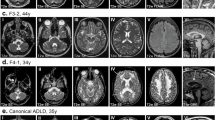

Activity of CID 662896 and CID 5308648 in fibroblasts from ADLD patients

We then tested the two prioritized compounds in ADLD patient cells by Western blot. Figure 6 shows that CID 662896 significantly and dose-dependently reduced levels of endogenous LMNB1 in ADLD patient fibroblasts. In contrast, CID 5308648 showed only a minor and non-significant reduction trend (Fig. 6).

Activity of prioritized hits in ADLD patient cells. Cultured fibroblasts from ADLD patients were treated for 48 h with compounds. Lysates were immunoblotted with anti-LMNB1 and anti-beta actin antibodies. A and B. Representative Western blot of ADLD cells treated with CID 662896 or CID 5308648, respectively. Markers on the left indicate molecular weights in kDa. C and D. Quantification of CID 662896 and CID 5308648 response. LMNB1 / actin intensity ratios were normalized to DMSO controls. Data in C. and D. show mean ± SD of the indicated numbers of independent biological repeats. P-values were computed by one-way ANOVA with Holm-Šídák's multiple comparisons test.